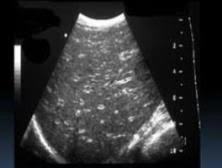

Starry sky pattern

Periportal edema in the setting of hepatitis